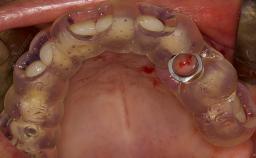

Complications of Sinus Floor Elevation

Sinus floor elevation using either the lateral window or transcrestal approach is a predictable surgical procedure with proven success, low complication rates, and high survival rates.

This learning module will provide an overview of the most commonly seen intraoperative and postoperative complications associated with sinus floor elevation and will discuss management in terms of preventative measures as well as treatment strategies.